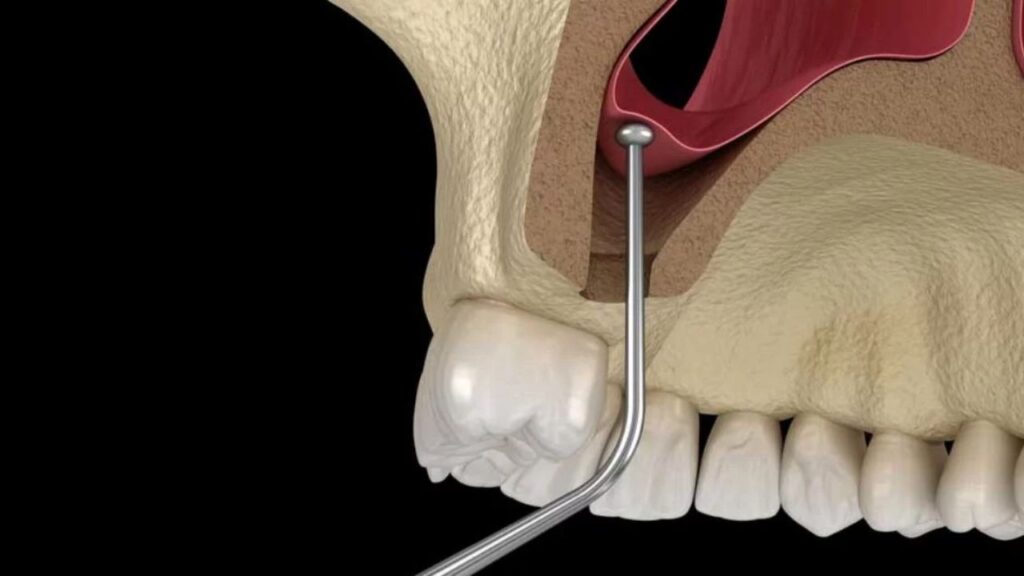

Manejo del seno maxilar

Procedimientos especializados para preparar el hueso maxilar en casos de implantes dentales, especialmente en pacientes con pérdida ósea significativa. La elevación del seno maxilar permite garantizar el éxito a largo plazo de los implantes.